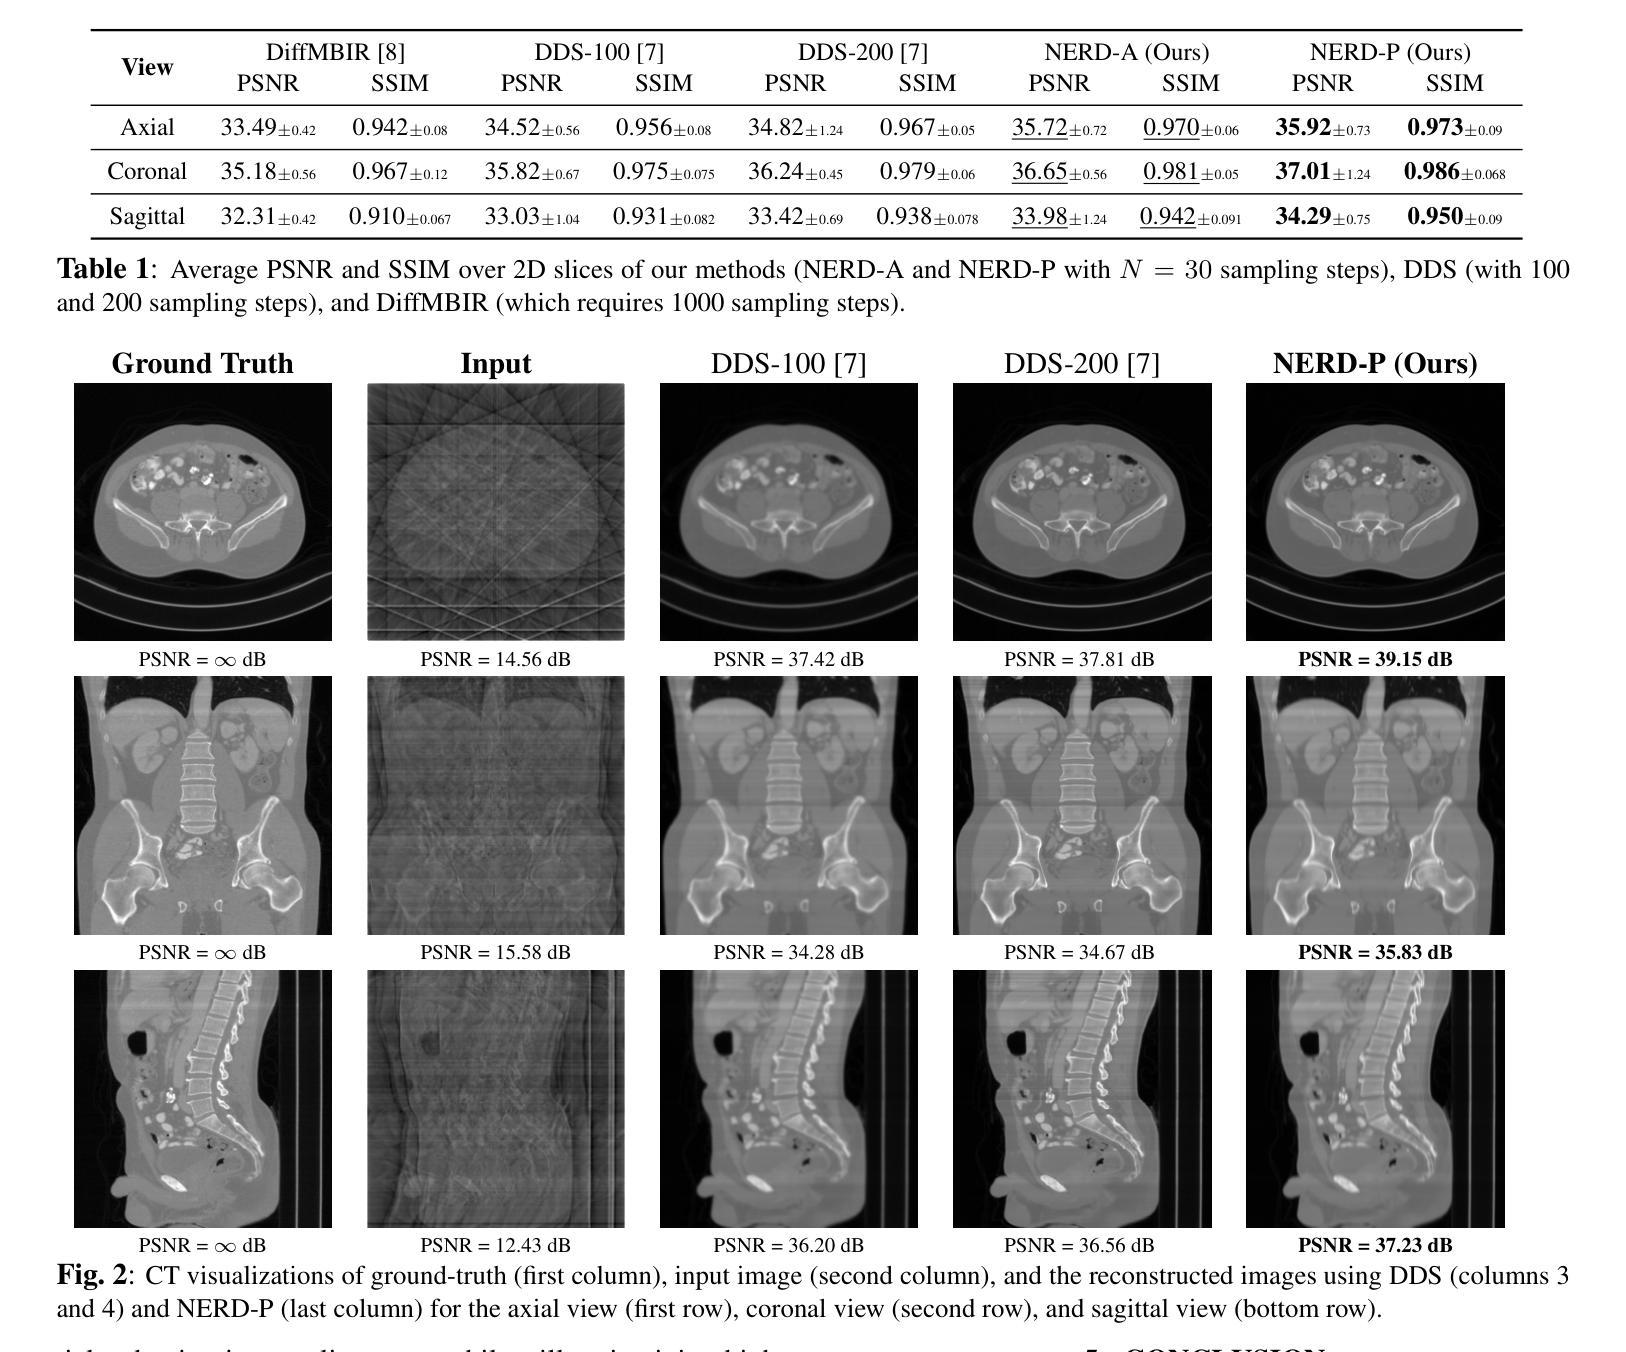

Numerous diffusion model (DM)-based methods have been proposed for solving inverse imaging problems. Among these, a recent line of work has demonstrated strong performance by formulating sampling as an optimization procedure that enforces measurement consistency, forward diffusion consistency, and both step-wise and backward diffusion consistency. However, these methods have only considered 2D reconstruction tasks and do not directly extend to 3D image reconstruction problems, such as in Computed Tomography (CT). To bridge this gap, we propose NEtwork-Regularized diffusion sampling for 3D CT (NERD) by incorporating an L1 regularization into the optimization objective. This regularizer encourages spatial continuity across adjacent slices, reducing inter-slice artifacts and promoting coherent volumetric reconstructions. Additionally, we introduce two efficient optimization strategies to solve the resulting objective: one based on the Alternating Direction Method of Multipliers (ADMM) and another based on the Primal-Dual Hybrid Gradient (PDHG) method. Experiments on medical 3D CT data demonstrate that our approach achieves either state-of-the-art or highly competitive results.

针对逆向成像问题,已经提出了许多基于扩散模型(DM)的方法。其中,最近的一项工作通过制定采样作为优化过程,强制执行测量一致性、正向扩散一致性以及逐步和反向扩散一致性,展现了强大的性能。然而,这些方法仅考虑了2D重建任务,并不能直接扩展到3D图像重建问题,例如在计算机断层扫描(CT)中。为了弥补这一差距,我们通过将L1正则化融入优化目标,提出了用于3D CT的网络正则化扩散采样(NERD)。这种正则化鼓励相邻切片之间的空间连续性,减少了切片间的伪影,促进了连贯的体积重建。此外,我们还引入了两种有效的优化策略来解决由此产生的目标:一种基于交替方向法乘数(ADMM),另一种基于原始-对偶混合梯度(PDHG)方法。在医疗3D CT数据上的实验表明,我们的方法达到了最前沿或高度竞争的结果。